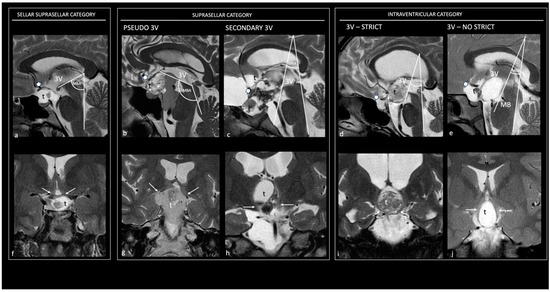

4.1.1. Topographical Classifications

- Prieto, R.; Pascual, J.M.; Barrios, L. Topographic Diagnosis of Craniopharyngiomas: The Accuracy of MRI Findings Observed on Conventional T1 and T2 Images. AJNR Am. J. Neuroradiol. 2017, 38, 2073–2080. [Google Scholar] [CrossRef] [PubMed]

- Pascual, J.M.; González-Llanos, F.; Barrios, L.; Roda, J.M. Intraventricular Craniopharyngiomas: Topographical Classification and Surgical Approach Selection Based on an Extensive Overview. Acta Neurochir. 2004, 146, 785–802. [Google Scholar] [CrossRef]

- Pascual, J.M.; Prieto, R.; Carrasco, R. Infundibulo-Tuberal or Not Strictly Intraventricular Craniopharyngioma: Evidence for a Major Topographical Category. Acta Neurochir. 2011, 153, 2403–2425. [Google Scholar] [CrossRef]

- Prieto, R.; Barrios, L.; Pascual, J.M. Strictly Third Ventricle Craniopharyngiomas: Pathological Verification, Anatomo-Clinical Characterization and Surgical Results from a Comprehensive Overview of 245 Cases. Neurosurg. Rev. 2022, 45, 375–394. [Google Scholar] [CrossRef] [PubMed]

| Topography | PCP | Pascual et al., 2013 [24] | Frequently strictly intraventricular CPs |

| ACP | Pascual et al., 2013 [24] | Variable presence of sellar–suprasellar, pseudointraventricular, secondary intraventricular, and not-strictly intraventricular CPs | |